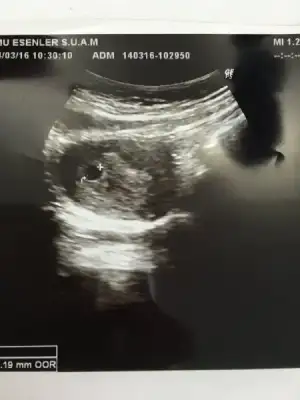

KIZLAR ÇOK ŞÜKÜR BUGÜN KESEMİZİ KARINDAN ULTRASONLA GÖRDÜK 2 HAFTA SONRA GEL DEDİ DR KALP ATIŞLARI İÇİN ALLAHIM NASIL GÜZEL BİR DUYGU İNŞALLAH HEPİMİZ SAĞLIKLA KUCAĞIMIZA ALIRIZ

BU DA KESEMİZ DOKTOR ÇOK GÜZEL DEDİ MAŞALLAH HERKES KIZIN OLCAK DİYO NORMALDE KIZ ÇOCUKLARINI PEK SEVİMLİ BULMAM NEDENSE BENİMDE GÖNLÜMDEN GEÇEN KIZ

hayırlı olsun canım kac mm:)BU DA KESEMİZ DOKTOR ÇOK GÜZEL DEDİ MAŞALLAH HERKES KIZIN OLCAK DİYO NORMALDE KIZ ÇOCUKLARINI PEK SEVİMLİ BULMAM NEDENSE BENİMDE GÖNLÜMDEN GEÇEN KIZ

CANIM DOKTORUN DEDİĞİNE GÖRE 4 HAFTALIK BENİMDE SATA GÖRE 5+6 HAFTALIK AMA O FARK ZAMANLA KAPANIYORMUS KAC MM OLDUGUNU SORMADIMkaç

Canım ultrason kağıdının sğ altta yazıyor GS 0.88 CM yazıyor mesela bendeCANIM DOKTORUN DEDİĞİNE GÖRE 4 HAFTALIK BENİMDE SATA GÖRE 5+6 HAFTALIK AMA O FARK ZAMANLA KAPANIYORMUS KAC MM OLDUGUNU SORMADIM

CANIM EKTE FOTOSU SEN Bİ BAK İSTERSE BENDE 11.0 CM YAZIYO SANIRIMCanım ultrason kağıdının sğ altta yazıyor GS 0.88 CM yazıyor mesela bende